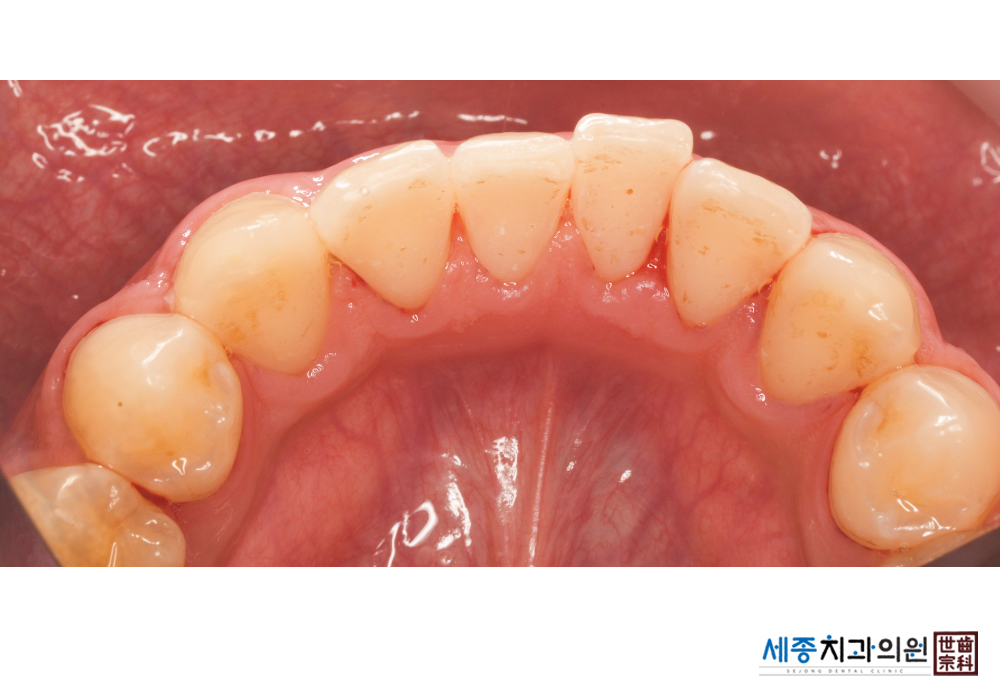

[스케일링] 치주질환 예방 스케일링

치료전 : 2020-01-20

가글마취&저주파 스켈러를 사용한 스케일링